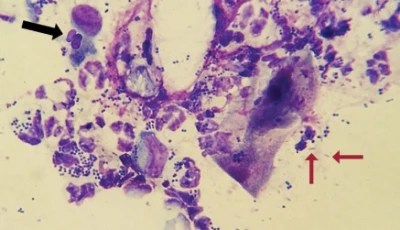

It tells us whether there is a bacterial or yeast infection in the ear causing redness, itchiness, head shaking, and other signs. This can be observed by taking an ear swab sample, which is then stained and checked under the microscope.

Next, the swab tips are rolled onto a clean slide gently to transfer the material. The samples are allowed to air dry and then stained. The slides are then carefully scanned under the microscope for cells, larger structures, and bacteria.